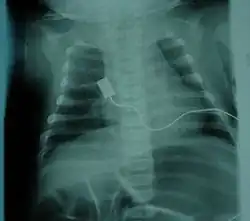

- Loss of strength of the respiratory muscles: weak cough, weak cry (infants), accumulation of secretions in the lungs or throat, respiratory distress

- Bell-shaped torso (caused by using only abdominal muscles for respiration) in severe SMA type

The respiratory system is the most common system to be affected, and the complications are the leading cause of death in SMA types 0/1 and 2. SMA type 3 can have similar respiratory problems, but it is rarer.[24] Complications arise due to weakened intercostal muscles because of the lack of stimulation from the nerve. The diaphragm is less affected than the intercostal muscles.[24] Once weakened, the muscles never fully recover the same functional capacity to help in breathing and coughing, as well as other functions. Therefore, breathing is more difficult and poses a risk of not getting enough oxygen/shallow breathing, and insufficient clearance of airway secretions. These issues more commonly occur while asleep, when muscles are more relaxed. Swallowing muscles in the pharynx can be affected, leading to aspiration coupled with a poor coughing mechanism increases the likelihood of infection/pneumonia.[59] Mobilizing and clearing secretions involve manual or mechanical chest physiotherapy with postural drainage, and manual or mechanical cough assistance device. To assist in breathing, Non-invasive ventilation (BiPAP) is frequently used and tracheostomy may be sometimes performed in more severe cases;[60] both methods of ventilation prolong survival to a comparable degree, although tracheostomy prevents speech development.[61]